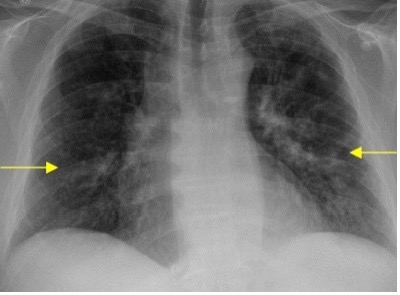

55 y/o F admitted for MRSA bacteremia, started on dapto, dificult dispo, on week 3 when we are ready to send her home she started to complain of sob, cough, she had fevers, her labs showed peripheral eosinophilia, she is hypoxic. the xray is showing

What is the most likely dx and next best step??????

Daptomycin eosinophilic pneumonia!!!

usually 2-4 weeks after starting dapto, classic sx: respiratory, pulmonary infiltrates and eosinophilia.

dx: BAL confirming eosinophils > 25%

tx > stop dapto asap and start steroids!